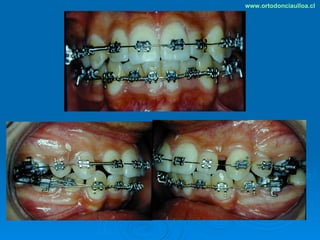

Este documento presenta dos casos clínicos de pacientes que recibieron tratamiento de ortodoncia. El primer caso fue de una paciente femenina de 14 años con apiñamiento dental y mordida cruzada que fue tratada mediante extracción de premolares y alineamiento dental. El segundo caso fue de un paciente masculino de 14 años con clase II esqueletal y desarmonía dentomaxilar que fue tratado con extracción de premolares y corrección de mordida. Ambos casos mostraron mejoría después de 3 años de tratamiento.